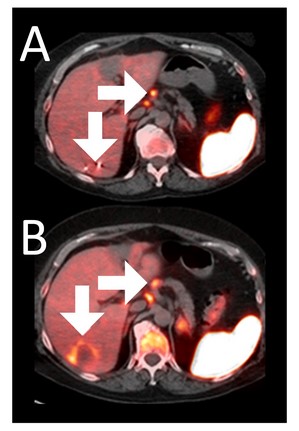

Before BriaCell Treatment Image A: A liver metastasis (lower arrow) is “cold,” indicating minimal to no CD8+ cytotoxic T cells in the tumor while enlarged lymph nodes (upper arrow) show moderate uptake.

After BriaCell Treatment Image B: Swelling (induration) around the metastasis (lower arrow) demonstrates the liver metastasis has become “hot”, indicating marked CD8+ cytotoxic T cell infiltration while further lymph node enlargement is consistent with increased activity (upper arrow) indicating increased CD8+ T cells.

Example 3 Images (Patient 15-006): Combined MRI and CD8 ImmunoPET images Pre (A) and Post (B) Bria-IMT treatment